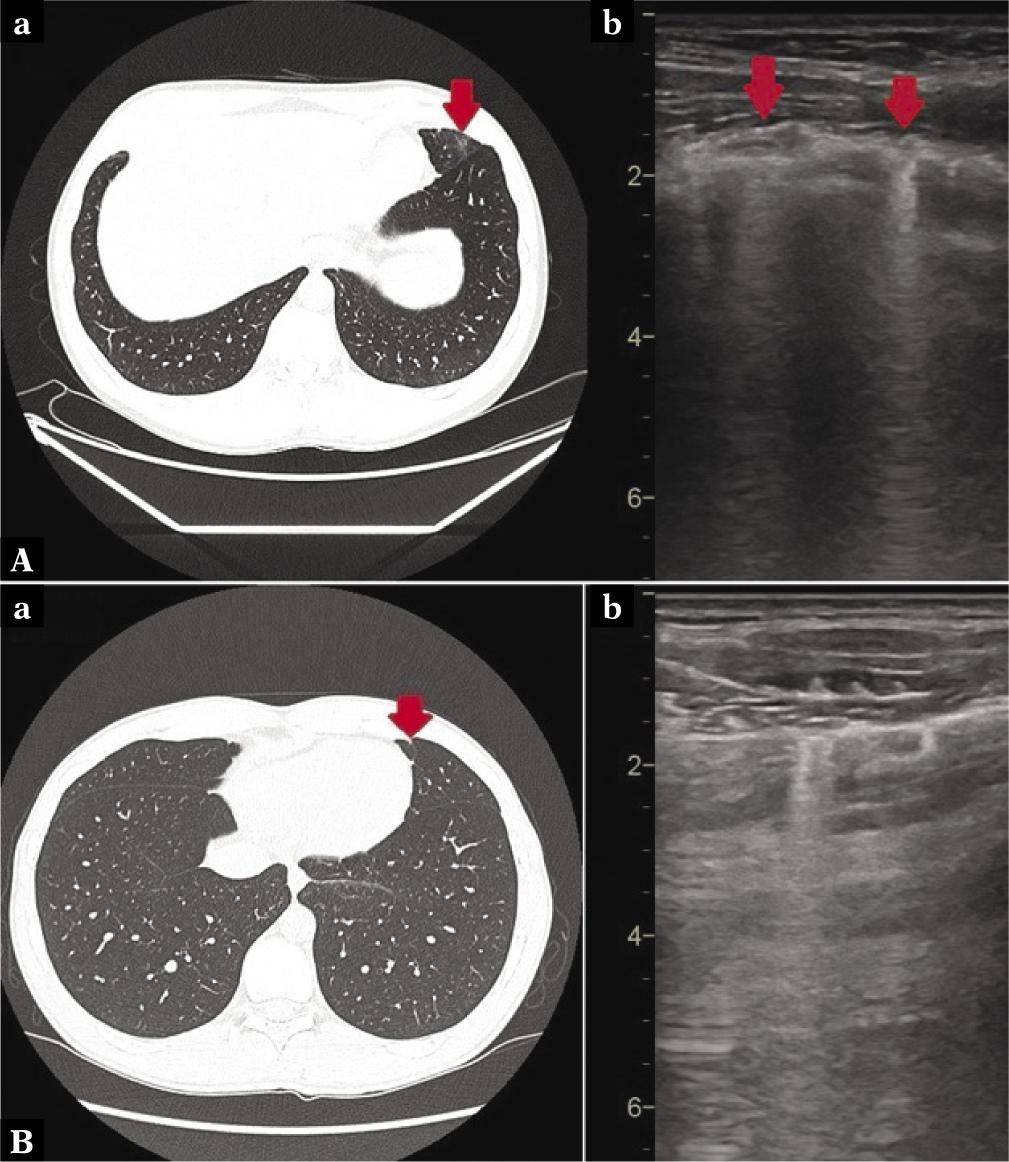

Fig. 2.

Pattern of changes visible on HRCT

Pattern of changes visible on LUS

| Number of areas with consolidations | 59 | 7 (12.5%) | 29 (12.6%) | 21 (16.7%) | 2 (14.3%) |

| 1) Big consolidations with thick C-line | 25 | 2 | 12 | 10 | 1 |

| 2) Small consolidations | 45 | 6 | 24 | 14 | 1 |